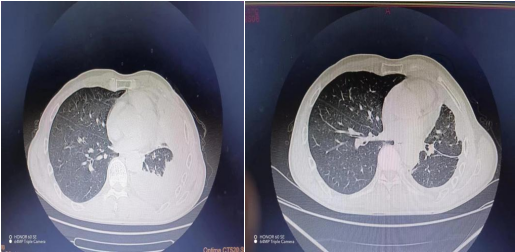

患者蔡先生,因“胸闷、气喘1周”入院,入院后行胸部CT示:左侧胸腔大量积液伴左肺膨胀不全。经章秀主治医师、熊琪住院医师分析病情后,制定诊疗方案,考虑左侧大量胸腔积液压缩肺不张引起胸闷气喘,予以完善术前准备,在B超定位引导下行胸腔引流术,先后引流出大量积液,随之患者胸闷气喘症状逐渐好转。下图所示前后五天变化。